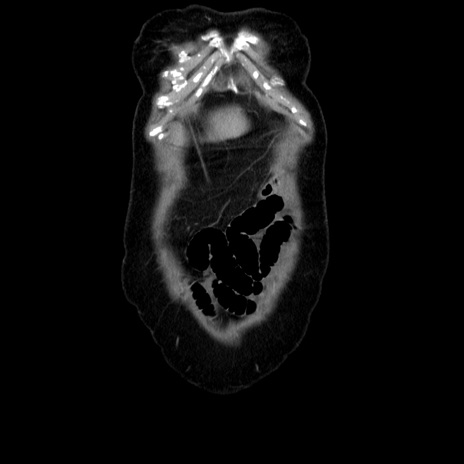

横断像

【症例】70歳代女性

【主訴】お腹が張る

【現病歴】1週間くらい前から腹部膨満の自覚あり。昨日夜から増悪したため、本日救急外来受診。

【身体所見】意識清明、BT 36.5℃、BP 165/106mmHg、HR 80bpm、SpO2 98%、腹部:膨満、軟、自発痛・圧痛なし、触診にて不快感あり、腸蠕動音:減弱

【データ】WBC 12600、CRP 1.04